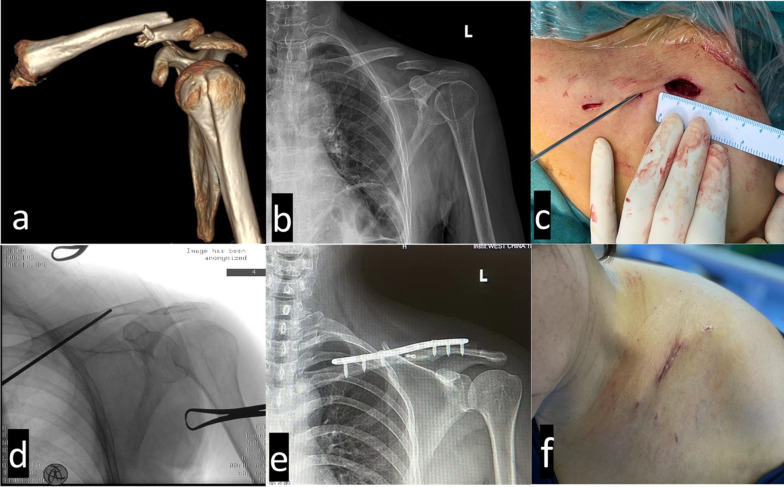

Methods: We retrospectively reviewed 45 cases of displaced midclavicular fractures that were treated surgically at our hospital between December 2020 and June 2022. There were 20 (44.4%) patients using mini-open with MIPO and 25 (55.6%) patients using conventional ORIF treated with anatomical locking plate guided by C-arm X-ray machine. Comparison of surgical indices (operative time, blood loss, incision length, and fluoroscopy exposure times) and postoperative complications (anterior chest wall numbness, area of numbness, superficial infection, hardware irritation, and scar satisfaction) were compared between the two groups. In addition, Disabilities of the Arm, Shoulder and Hand (DASH), Constant-Murley Score (CMS), and overall surgical satisfaction were compared between the two groups.

Results: The mini-open MIPO group had statistically significant benefits on the basis of surgical length, blood loss, visual analog scale (VAS) score on the first and third postoperative days, and length of hospital stay. Major complications, such as SCN-related numbness, area of numbness, and thick scarring, were greatly reduced. The cosmetic and overall surgical satisfaction was greater in MIPO. Conversely, hardware irritation, surgical infection, and numbness were more frequent in the ORIF group. There were no significant differences in DASH and CMS scores between the groups at the 12-month follow-up.

Conclusions: MIPO is a more effective and safer modern surgical method than ORIF for displaced midclavicle fractures. Improvements in operative indices, postoperative numbness owing to SCN injury, surgical incision, and cosmesis satisfaction were achieved.